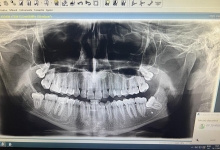

Clinica LUY ESTHETIC ART defineste parodontoza ca fiind rezultatul direct al placii dentare, care se depune pe suprafata dintilor, dar si in apropiere de marginea gingivala. Aceasta boala duce la pierderea dintilor, chiar daca ei sunt aparent sanatosi si nu prezinta carii. Edentatiile, afecteaza vorbirea, aspectul, dar si capacitatea de a mesteca.

Boala parodontala are un caracter progresiv. Pentru cazurile mai grave, recomandam tratamentul parodontal chirurgical rezectiv sau regenerativ.

O igiena bucala necorespunzatoare, fumatul, placa bacteriana si alte boli generale, permit bacteriilor sa se dezvolte in cavitatea bucala.